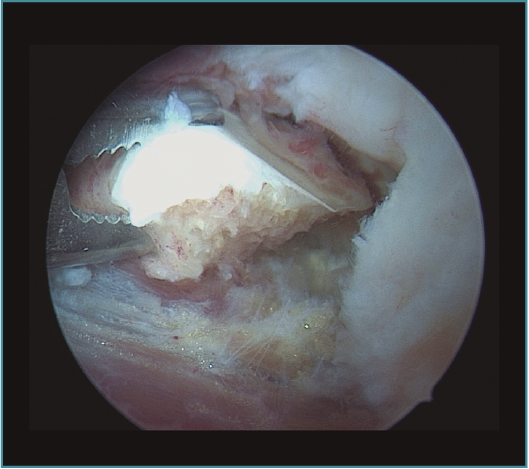

Seguidamente trabajaremos en la cámara posterior del codo, utilizando el portal transtricipital central como portal de visión y el portal posterolateral como portal de trabajo (estos portales van cambiando su función durante la cirugía y podemos añadir portales centrales y laterales más proximales, así como el portal lateral directo o soft spot)(20). No utilizamos el portal posteromedial para no poner en riesgo el nervio cubital, siguiendo las recomendaciones de Hilgersom, entre otros autores(18). En la parte posterior trabajaremos con el mismo orden: primero la resección de osteofitos en punta de olécranon, foseta olecraniana y parte lateral y medial del codo, así como extracción de cuerpos libres o tratamiento de lesiones osteocondrales en la parte posterior del cóndilo lateral del húmero (localización más frecuente), con desbridamiento del tejido inestable y/o perforaciones. Tras la parte ósea, realizaremos la capsulotomía posterior, para ganar flexión del codo (Vídeo, minutos 2:46-4:25; Figuras 9 a 14).

Figura 13. Caso 6. Visión artroscópica de la resección del fragmento osteocondral inestable del cóndilo humeral. En este caso, desde la cámara posterior del codo, con la óptica en el portal posterior central y las pinzas en el portal posterolateral.

Figura 14. Caso 6. Visión artroscópica desde el portal anteromedial tras la resección del fragmento osteocondral del cóndilo humeral; se aprecia la articulación del cóndilo con la cabeza humeral.